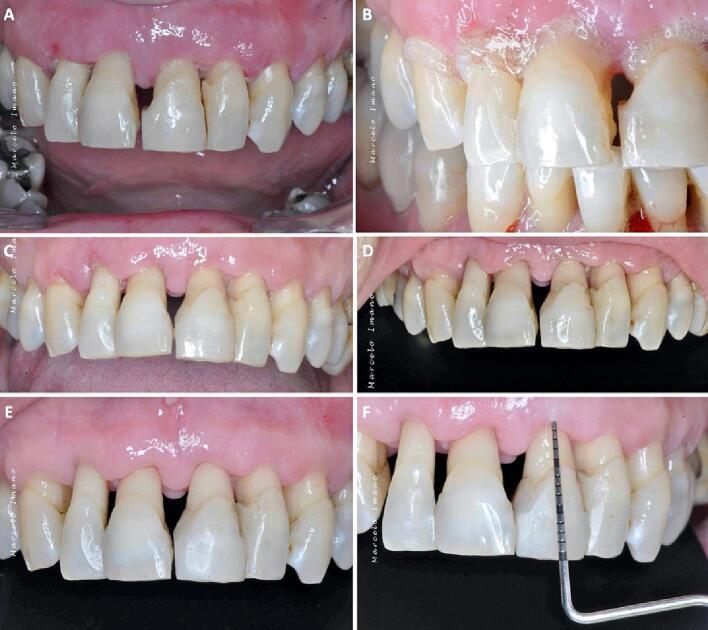

Globally, oral infections and inflammatory lesions persist as substantial public health concerns, necessitating the introduction of novel oral treatment protocols. Oral diseases are linked to various causative factors, with dental plaque/biofilm resulting from inadequate hygiene practices playing a predominant role. The strategic implementation of novel topical therapies holds promise for effectively controlling the biofilms, addressing oral infections and promoting enhanced oral wound healing. This review aims to providing a comprehensive overview of the available evidence pertaining to the potential efficacy of topical oxygen and lactoferrin-releasing biomaterials, exemplified by the blue®m formula, as novel oral care interventions within the scope of contemporary implantology, oral surgery and periodontology.

在全球范围内,口腔感染和炎性病变仍然是重大的公共卫生问题,因此需要引入新的口腔治疗方案。口腔疾病与多种致病因素相关,其中因卫生习惯不良导致的牙菌斑/生物膜起着主要作用。新型局部治疗方法的战略实施有望有效控制生物膜、解决口腔感染并促进口腔伤口愈合。本综述旨在全面概述有关局部用氧和释放乳铁蛋白的生物材料(以blue®m配方为例)作为当代种植牙学、口腔外科和牙周病学范围内新型口腔护理干预措施的潜在疗效的现有证据。